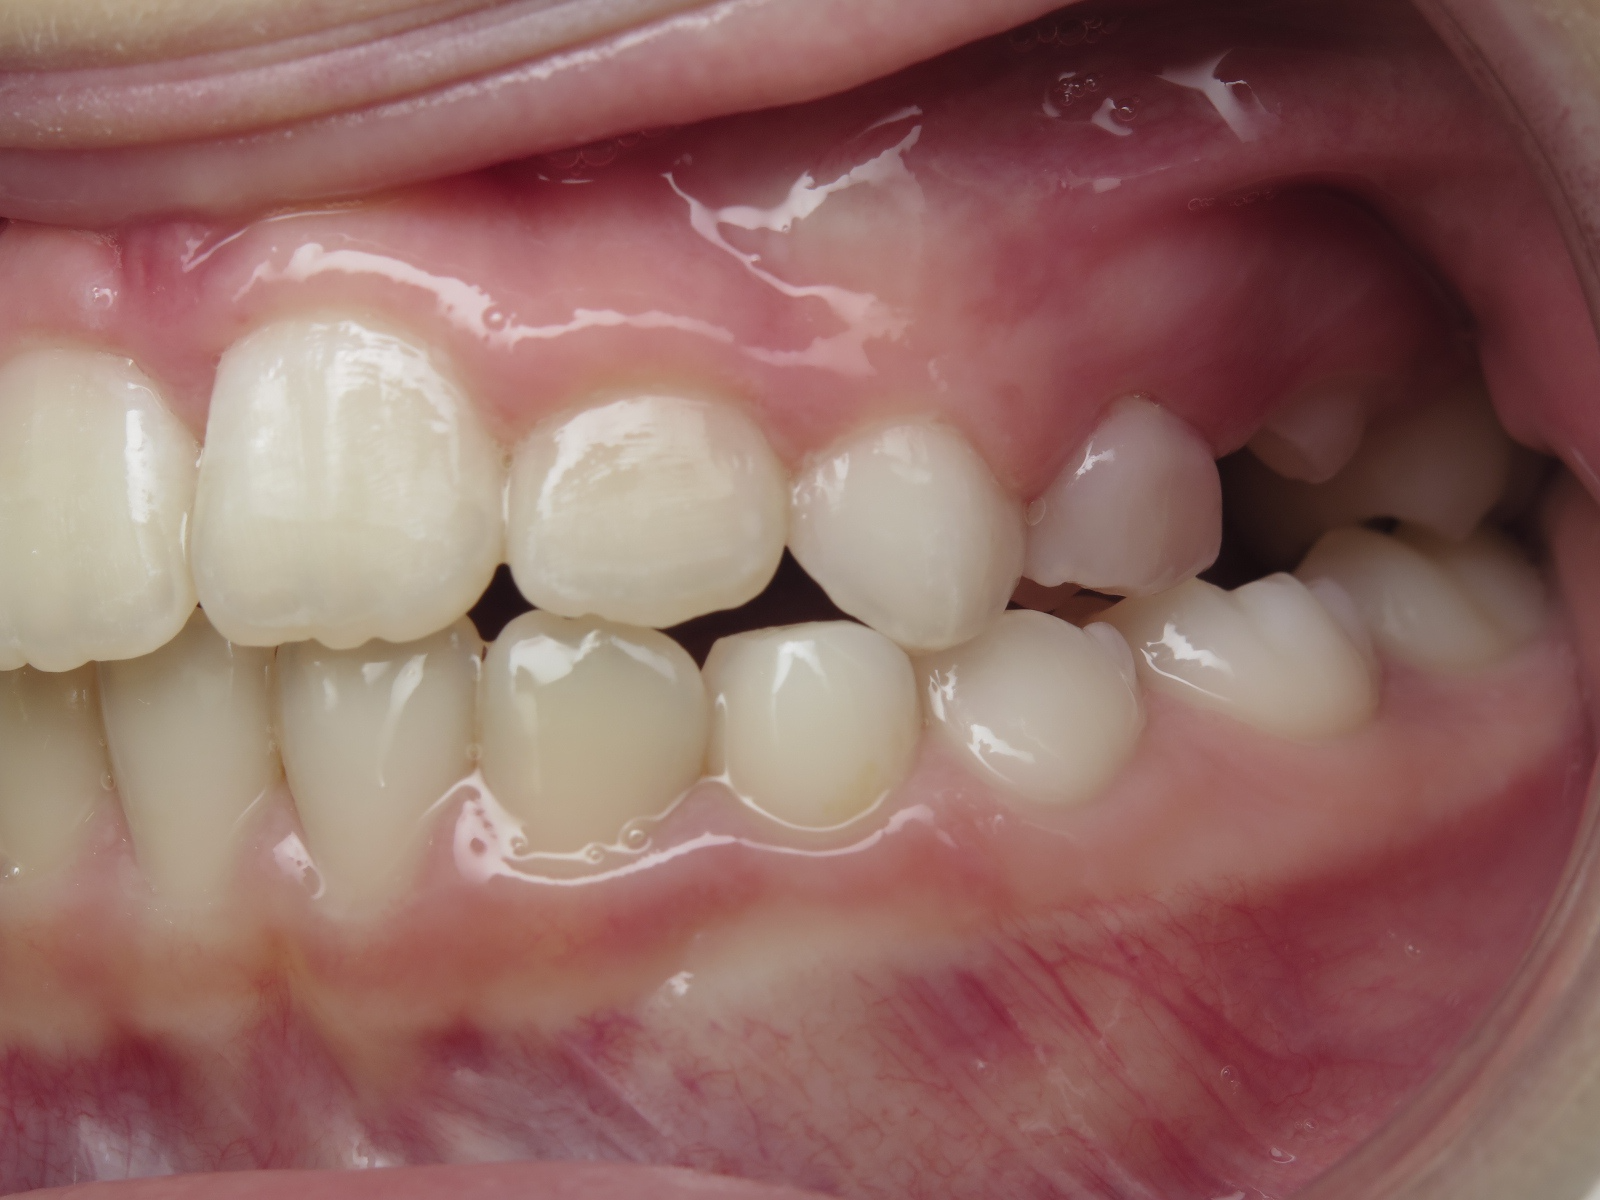

appareillage mobile pendant 22 mois

bilan début et en cours de traitement